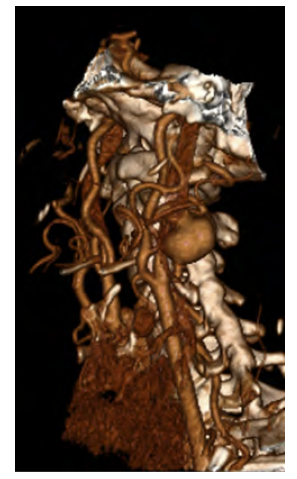

61-year-old female with a history of hypertension, dyslipidemia, and plunging goiter presents with an asymptomatic 17mm type I saccular aneurysm of the internal carotid artery (Figure 2). No aneurysms were found in other vascular territories. Underlying auto-immune diseases were excluded, and imagological findings did not suggest fibromuscular dysplasia. Aneurysmectomy and direct reconstruction through an end-to-end anastomosis were possible due to artery redundancy. Intraoperative cerebral perfusion monitoring was performed with INVOS™ without significant drop after carotid clamping, thus shunt placement was waived. Single antiplatelet therapy with acetylsalicylic acid was initiated in the immediate postoperative period and maintained lifelong. The patient reported complaints of facial hypoesthesia after surgery, which improved after the 12th month of follow-up. Anatomopathological findings showed an artery wall with extensive hyalinization and areas of myxoid degeneration of inconclusive etiology.

Figure 2 Pre-operative computed tomography angiography. 3D reconstruction showing a type I aneurysm of the internal carotid artery.

36-year-old male with a history of Cushing's syndrome due to a secretory adenoma of the pituitary gland presented with a 19mm type II fusiform aneurysm of the internal carotid artery (Figures 3A and B). Contralateral internal carotid and basilar ectasia were also found. After pituitary gland tumor resection, he underwent arterial reconstruction with an interposition using a saphenous vein graft (Figure 3C). Intraoperative cerebral perfusion monitoring was performed with INVOS™ without significant drop after carotid clamping, and the use of a shunt was unnecessary. The autologous conduit was preferred, given the need for chronic corticotherapy to prevent the risk of graft infection. The patient was kept under single antiplatelet therapy with acetylsalicylic acid to be continued lifelong. No complications were observed by the 8th month of follow-up. Histological findings showed atherosclerotic plaque in the initial stage with an area of arterial wall dissection but with no findings of fibromuscular dysplasia.

Figure 3 Pre-operative computed tomography angiography and Intra-operative images. A - 3D reconstruction showing a type II aneurysm of the internal carotid artery; B - carotid bifurcation and type II fusiform aneurysm of the internal carotid artery prior to reconstruction; C - reconstruction with a saphenous vein interposition.